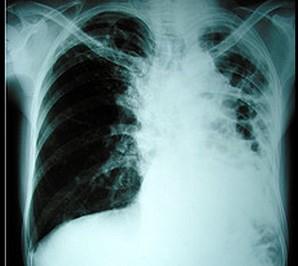

患者因咳嗽、胸痛、乏力入院,体检时发现左肺呼吸音减弱,X线胸片如图所示,诊断为 ( )A、肺癌B、以上均不正确C、自发性气胸D、肺结核...

问题 患者因咳嗽、胸痛、乏力入院,体检时发现左肺呼吸音减弱,X线胸片如图所示,诊断为 ( )

选项 A、肺癌 B、以上均不正确 C、自发性气胸 D、肺结核 E、支气管扩张

答案 D